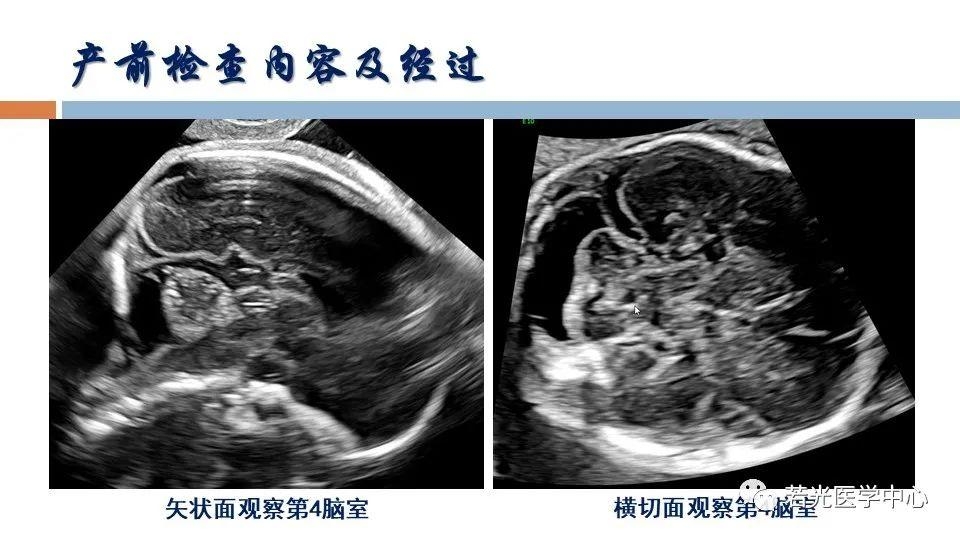

(6)表型-征象-分子遗传联合分析,遗传咨询分析与分子诊断。产前胎儿影像(超声,MRI)等异常,各类胎儿先天畸形与出生缺陷表型-基因-家系遗传分析,产前产后胎儿异常分析咨询,生育健康咨询。